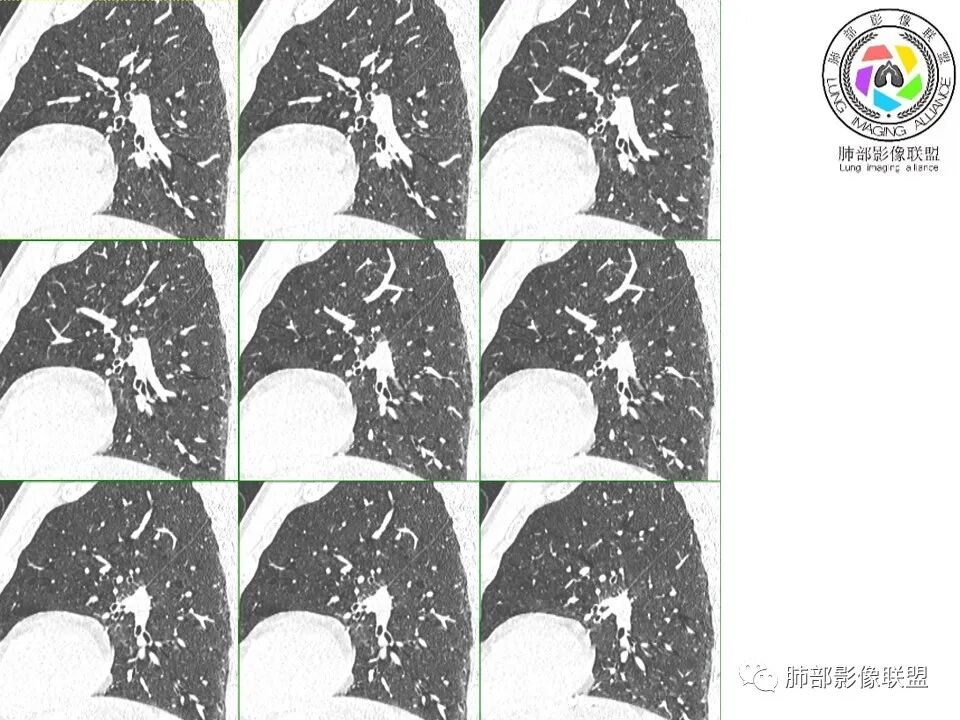

凝睦 (靳文剑): 左上肺结节,边缘不清,与胸膜广基底相连,刀切征,胸膜弥漫均匀增厚,考虑炎性。

采莲: 年龄不知,应该中老年男性,查体发现,左肺上叶靠近肺门斜裂附近实性结节影,边缘毛糙,周围有淡磨玻璃影,边界不清,其内及周围支气管稍扩张,考虑炎性肉芽肿,肺癌代排。

小兜: 晨读:一月前全身乏力就诊,CT示左肺上叶舌段近肺门及叶间胸膜结节,边缘不规则伴少量磨玻璃密度,与叶间胸膜相贴,叶间胸膜局部增厚伴略彭隆,未见明显牵拉。PET/CT代谢增高,SUVMax=9.8。综合考虑为炎性肉芽肿性病变,肺癌代排

衡妈: 肺气肿背景,左肺上叶舌段实性结节,边缘有分叶,毛刺,也有平直边,少许模糊感,临近叶间胸膜增厚,高代谢,考虑炎性肉芽肿,建议抗炎两周后复查,鉴别恶性肿瘤,腺癌。

丁云: 肺部联盟晨读病例:左肺上叶舌段不规则结节,有平直凹陷及膨隆,相邻血管穿行,支气管截断,血管贴边,胸膜增厚,PET高摄取,但也不是很高。首先考虑炎性肉芽肿。鉴别腺癌。

流心明智: 晨读:发现肺部阴影1月。左舌叶实性小结节,边缘平直、毛糙,短毛刺偏软,周围模糊晕,叶间胸膜广基增厚。右中叶小斑片影,考虑炎性肉芽肿,PC?鉴别Ca。

左肺上叶舌段近肺门区不规则结节,密度较均匀,结节边缘平直为主,可见粗短毛刺、毛刺偏软,浅分叶,收缩力不强,膨隆也不明显,周围可见模糊GGO,病灶内部支气管显示不清,病变远端支气管明显扩张,病灶与叶间裂呈宽基底相连,见刀切征,并见叶间裂多发结节影,叶间裂未见明显移位。